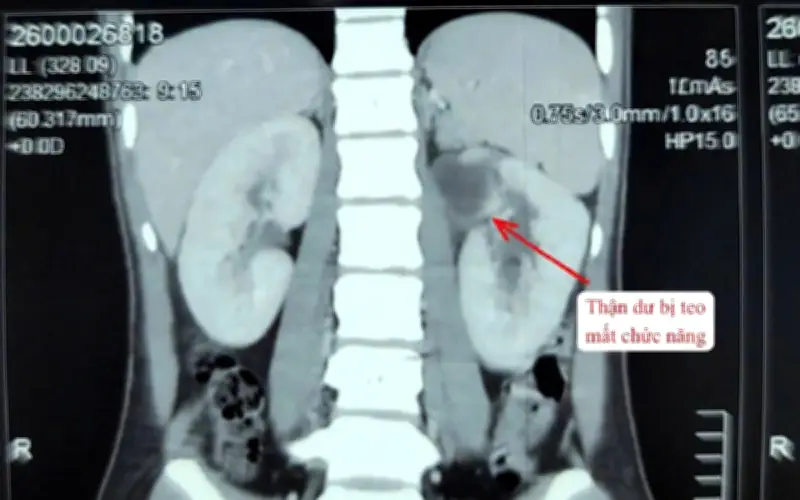

Qua thăm khám lâm sàng và các xét nghiệm cận lâm sàng chuyên sâu, các bác sĩ đã phát hiện bệnh nhân mắc dị tật thận - niệu quản đôi bên trái, với tổng cộng 3 thận. Trong đó, một thận đã hoàn toàn mất chức năng, kèm theo niệu quản giãn lớn bất thường và chứa đầy mủ, gây ra tình trạng nhiễm trùng nặng đe dọa sức khỏe.

Theo các chuyên gia y tế, đây là một dị tật bẩm sinh cực kỳ hiếm, chỉ xuất hiện ở khoảng 1% dân số, với tỉ lệ nữ giới mắc phải cao hơn nam giới. Dị tật này có thể dẫn đến các triệu chứng như nhiễm trùng tiết niệu tái phát, tiểu buốt, đau vùng hông lưng, hoặc thậm chí không biểu hiện rõ ràng, khiến việc phát hiện sớm trở nên khó khăn.